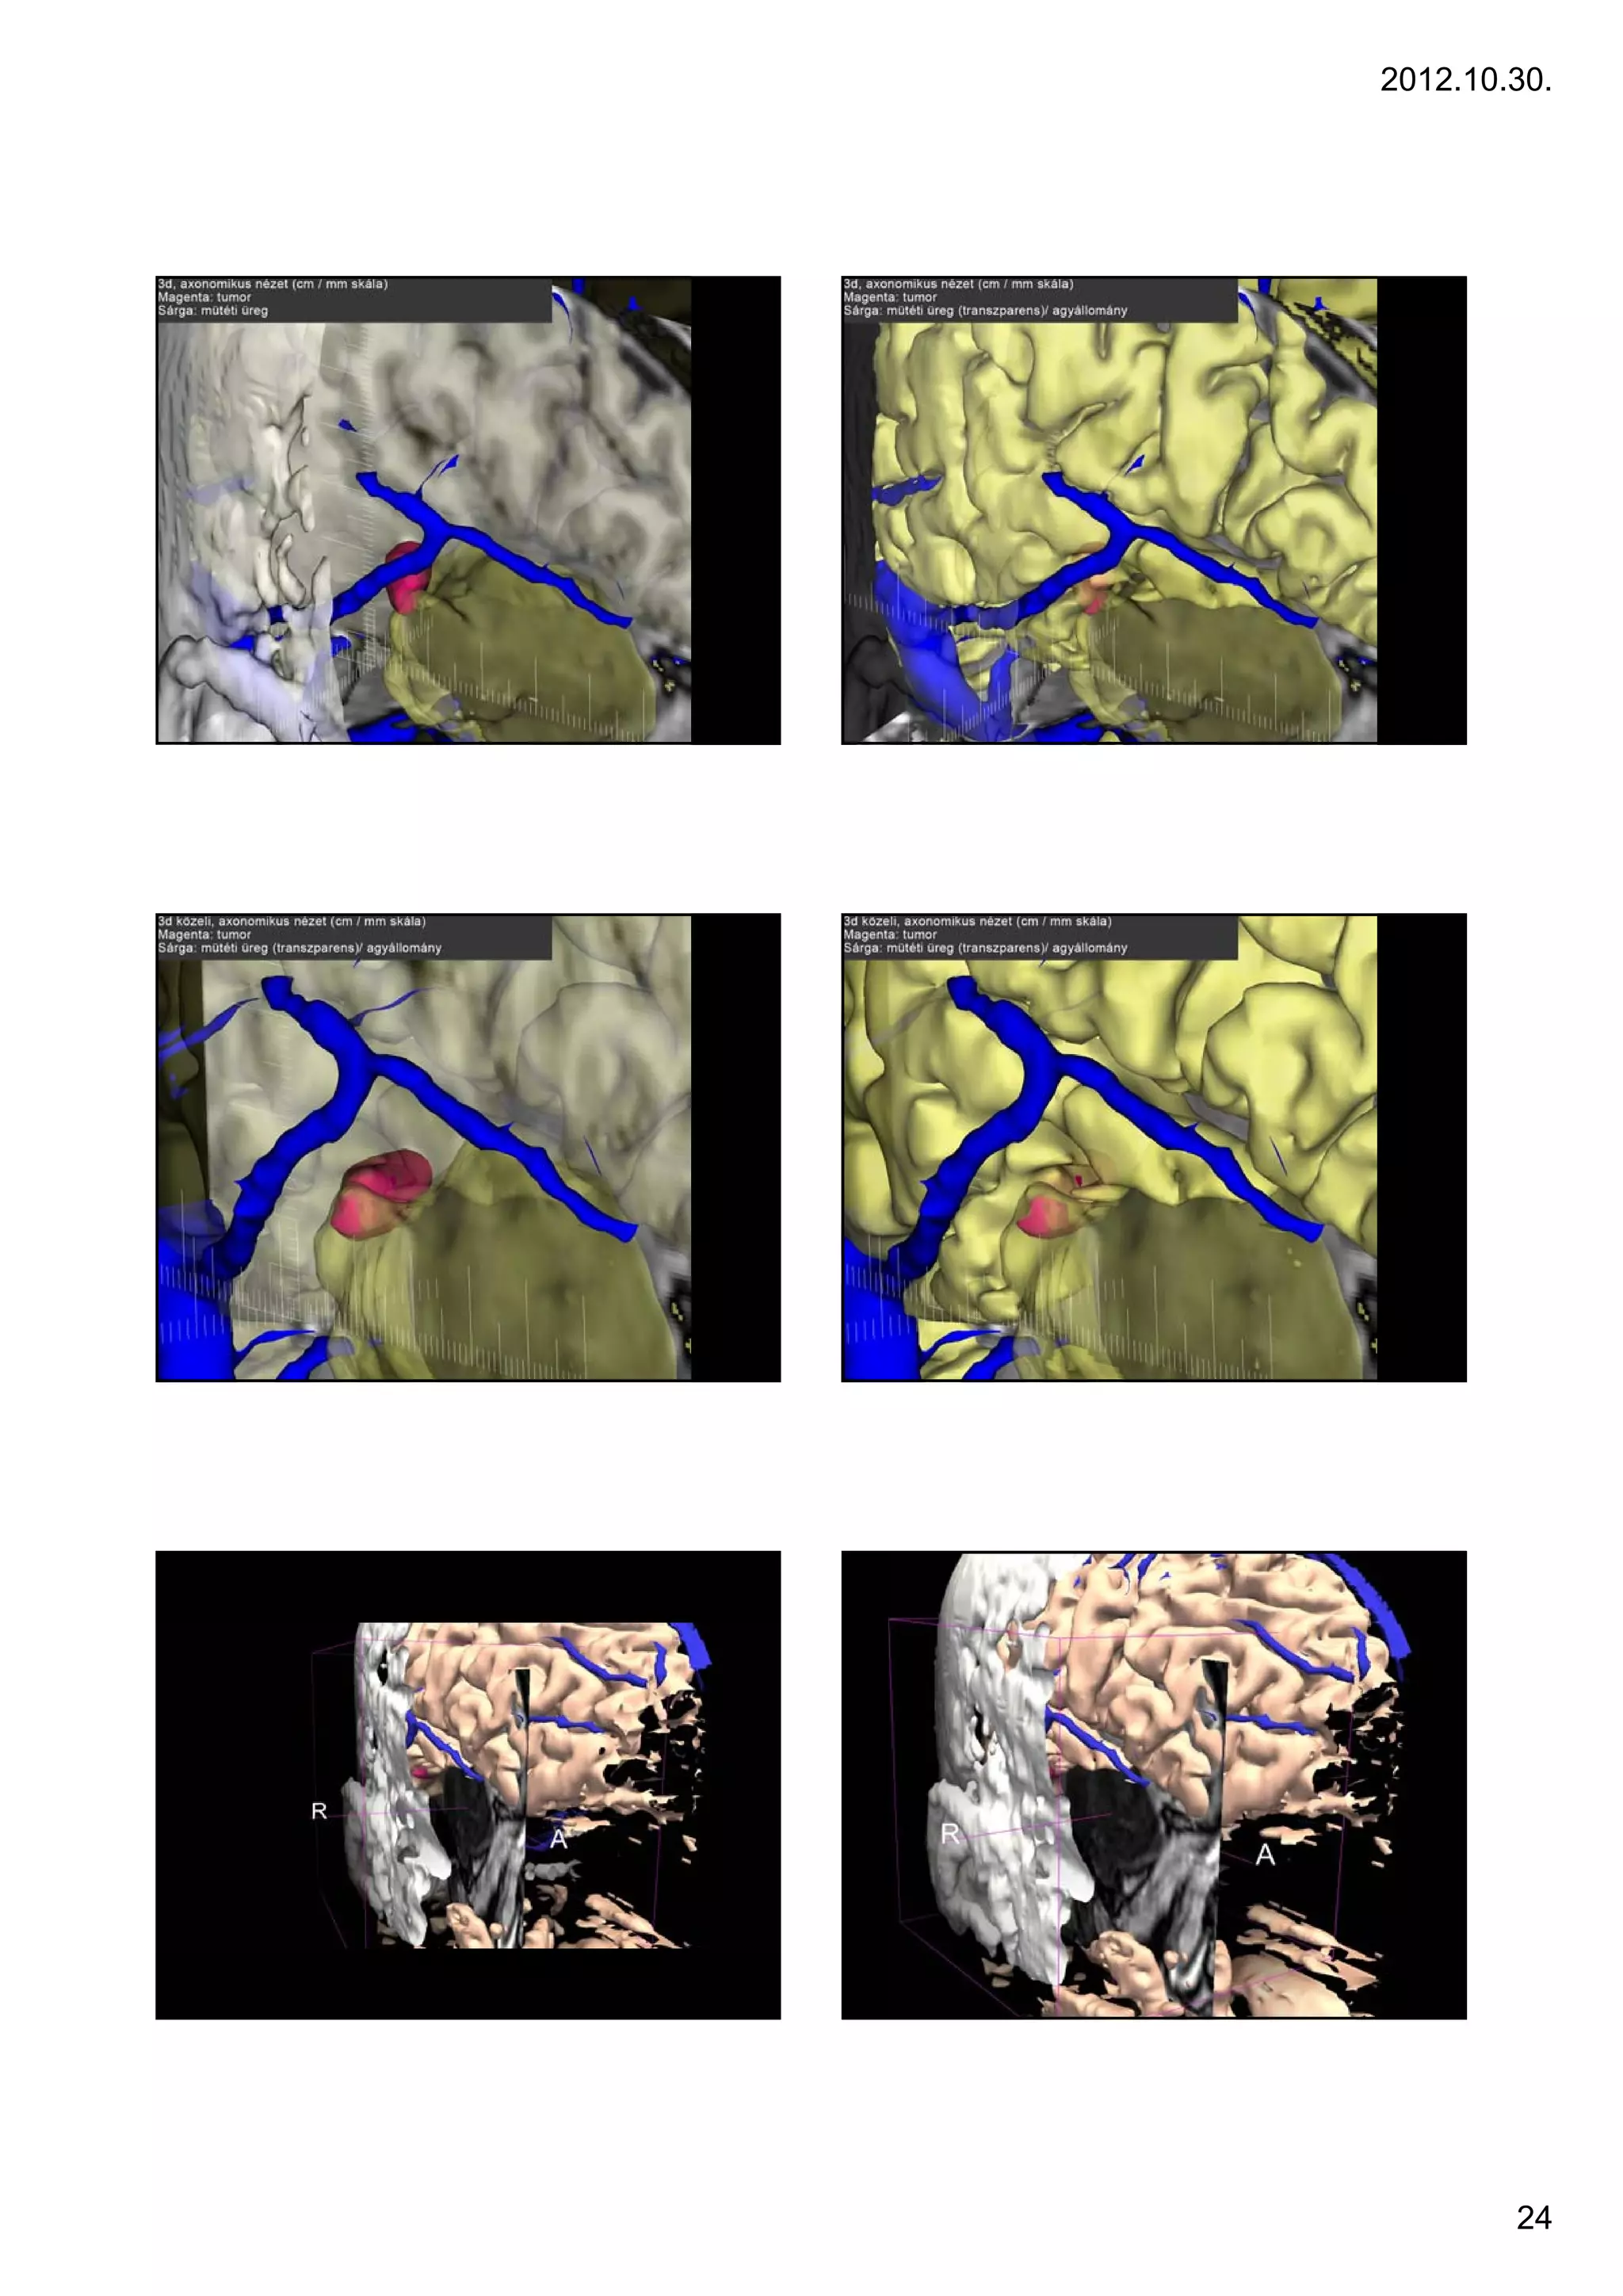

24

VISUALIZATION OF STRUCTURE

Recidive tumor, 2 foci, purple and magenta

Markers on the skin

removed temporal lobe parts

OPTIC RADIATION

CORTICOSPINAL TRACT

VISUALIZATION OF FIBERS

2012.10.30. VISUALIZATION OF STRUCTURE Recidive tumor, 2 foci, purple and magenta Markers on the skin removed temporal lobe parts Case 6 6. OPTIC RADIATION CORTICOSPINAL TRACT VISUALIZATION OF FIBERS 25